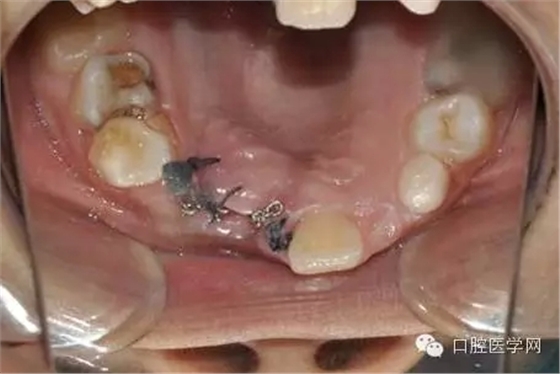

大量生理鹽水沖洗:

縫合后,要把鏈子留到外邊:

一周后拆線 :

術(shù)前已經(jīng)給小孩取了牙模,所以就開始

“活動(dòng)可調(diào)、釣魚式牽引器”的制作。(后續(xù)的博客會(huì)詳細(xì)的給大家講一下制作要領(lǐng),和各種卡環(huán)變異的彎制。簡(jiǎn)簡(jiǎn)單單的彎制卡環(huán)可以完勝各種焊接或鑄造。 )

帶入口內(nèi)調(diào)整吊桿方向加輕力:

(咬合調(diào)整好,加輕力激活)

每周復(fù)診:清洗,加力,適當(dāng)調(diào)整吊桿方向

用時(shí)9周完成埋伏牙牽引。